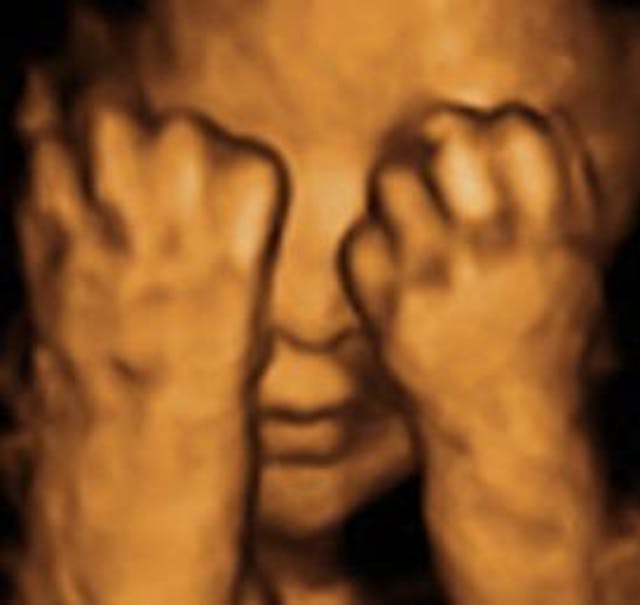

5) Hide and Go Seeker

This precious one looks like he’s playing games in his mom’s tummy. Now you see me and now you don’t. Pics like this are possible through places like Peek a Boo 3D/4D Ultrasound studios.